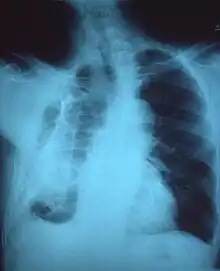

A fibrothorax can typically be diagnosed by taking an appropriate medical history in combination with the use of appropriate imaging techniques such as a plain chest X-ray or CT scan.[3] These imaging techniques can detect fibrothorax and pleural thickening that surround the lungs.[7] The presence of a thickened peel with or without calcification are common features of fibrothorax when imaged.[3] CT scans can more readily differentiate whether pleural thickening is due to extra fat deposition or true pleural thickening than X-rays.[3]

If a fibrothorax is severe, the thickening may restrict the lung on the affected side causing a loss of lung volume.[7] Additionally, the mediastinum may be physically shifted toward the affected side.[3] A reduction in the size of one side of the chest (hemithorax) on an X-ray or CT scan of the chest suggests chronic scarring.[6] Signs of the underlying disease causing the fibrothorax are also occasionally seen on the X-ray.[6] A CT scan may show features similar to those seen on a plain X-ray.[7] Lung function testing typically demonstrates findings consistent with restrictive lung disease.[6]